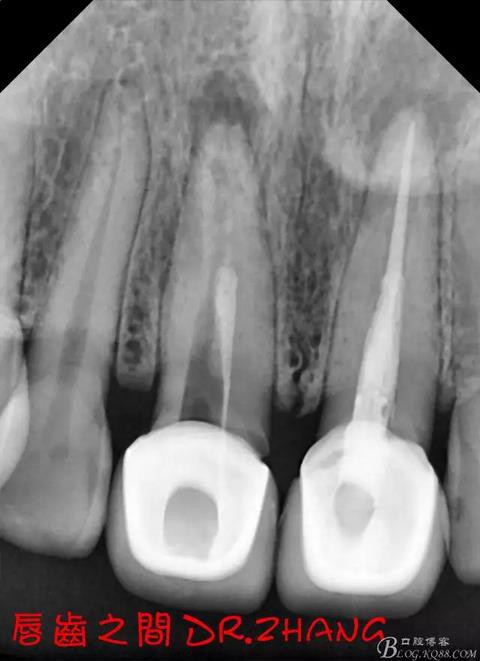

思博安熱牙膠系統(tǒng)根充 燙斷至根尖三分之一處后纖維樁恢復(fù)牙體組織

牙體預(yù)備后 硅橡膠取模 臨時牙恢復(fù)形態(tài)